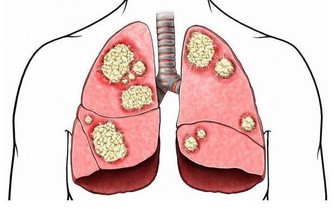

食物消化後的殘渣也要通過腸道排泄出去,如果這些垃圾堆積在體內不及時排出去,就會產生很多有害物質,引起腹漲、腹痛,甚至引起腸道擴張、誘發腫瘤。